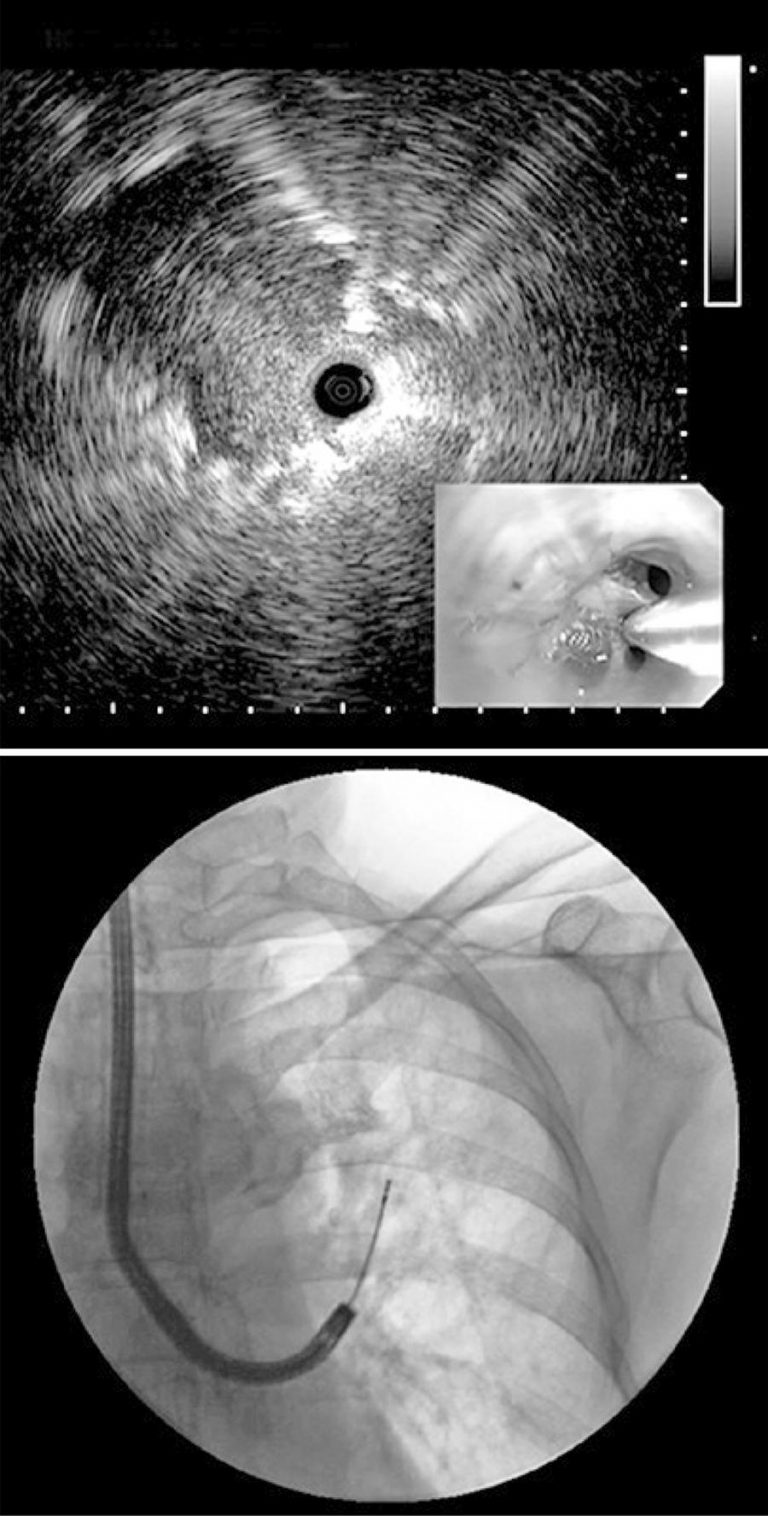

DOI: 10.31744/einstein_journal/2019MD4921

RESUMO A ultrassonografia endobrônquica é uma técnica minimamente invasiva que associa simultaneamente broncoscopia à ultrassonografia, com a finalidade de visualizar nódulos ou massas pulmonares, paredes das vias aéreas, e estruturas ao redor de toda a árvore traqueobrônquica. A ultrassonografia endobrônquica foi incorporada à prática clínica em todo o mundo devido a seu baixo risco e elevado rendimento diagnóstico em doenças neoplásicas e não neoplásicas.

Palavras-chave: Aspiração por agulha fina guiada por ultrassom endoscópico/métodos; Biópsia por agulha fina; Broncoscopia; Linfonodos; Mediastino; Ultrassonografia de intervenção